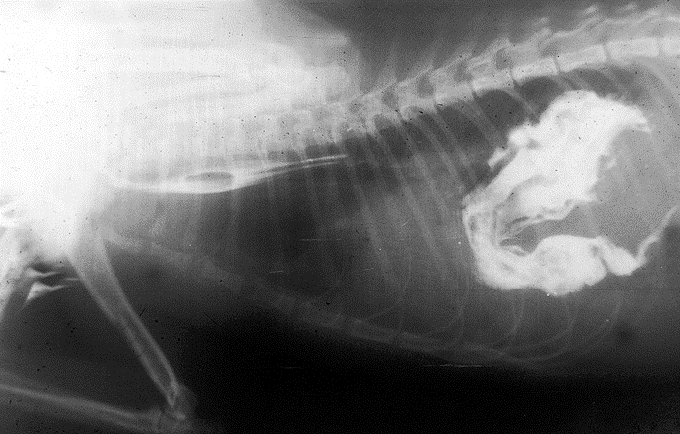

What does this show?

Vascular ring anomaly

Oesophagus is occluded by abnormal development at heart base

Will be regurgitating as soon as he is weaned